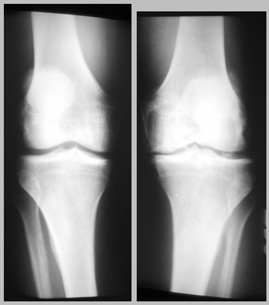

An X-ray of both my knees  looks like this:

This is taken as if you are standing in front of me and looking at my knees. The image on the left is my right knee and the image on the right is my left knee. (Confused yet?) They aren't really this close together when I'm standing, but PhotoShop makes all things possible. If you want a bigger image, click here.

My right knee looks pretty good, given the way I've abused it over the years. The left knee is another story. The tibia and femur show some spurring, and the medial meniscus has pretty much gone away (compare the gap between tibia and femur on either side of my left knee).